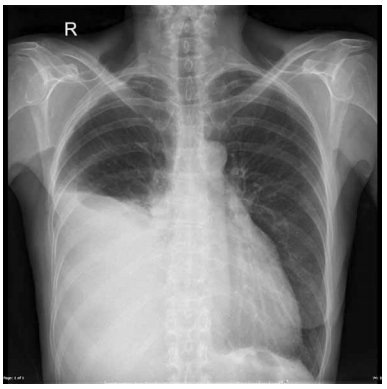

Homem, 35 anos, procura atendimento médico com queixa de tosse seca persistente e emagrecimento de 5 kg nos últimos 3 meses. Realizada radiografia de tórax que está ilustrada a seguir.

Realizada análise do líquido pleural, após toracocentese diagnóstica, que evidenciou: proteínas totais = 5,2 g/dL; DHL pleural = 380 U/L, glicose = 40 mg%, pH = 7,19, ADA = 59 UI/L. Dosagem sérica de proteínas totais = 6,8 g/dL; DHL sérico = 440 U/L. Realizada ainda biópsia pleural que evidenciou a presença de granulomas e pontos de necrose caseosa central.

Assinale a alternativa correta.